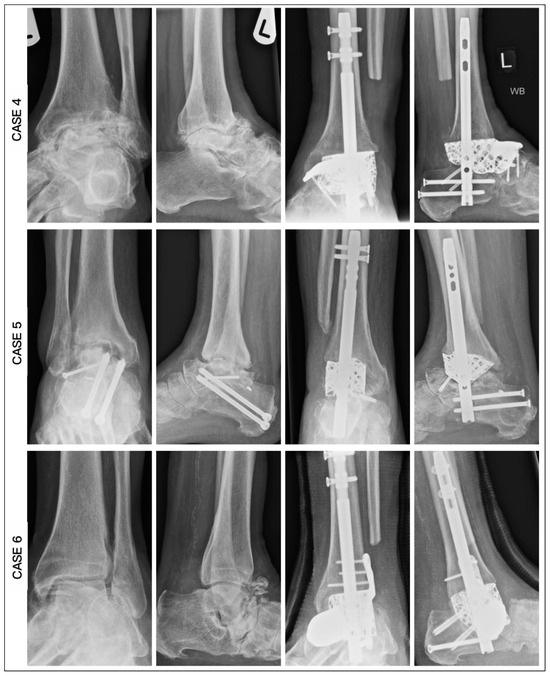

| CASE | 1 | 2 | 3 | 4 | 5 | 6 |

|---|---|---|---|---|---|---|

| Age | 62 | 59 | 60 | 60 | 78 | 67 |

| Diagnosis | OM | OM | OM | AVN | AVN | AVN |

| Modification | Tibial and Navicular Flange, Nail | Navicular Flange, Nail | Tibial and Navicular Flange | Navicular Flange, Nail | Nail | Articulating Navicular Extension, Tibial Flange, Nail |

| Union (weeks) | 25 | 19 | 16 | 14 | 27 | 20 |

| Ambulation (weeks) | 28 | 21 | 18 | 16 | 29 | 22 |

| Tibiocalcaneal angle (pre) | 38.4 | 18.6 | 12.4 | −6.8 | 13.8 | 10.5 |

| Tibiocalcaneal angle (post) | 6.2 | 3.0 | 3.4 | 4.2 | 6.1 | 4.2 |

| Difference | 32.2 | 15.6 | 9.0 | 11 | 7.7 | 6.3 |

| Tibiotalar angle (pre) | 16.1 | 4.4 | 12.4 | −6.1 | 11.9 | 2.1 |

| Tibiotalar angle (post) | 1.4 | 1.2 | 0.9 | 0.2 | 0.5 | 0.7 |

| Difference | 14.7 | 3.2 | 11.5 | 6.3 | 11.4 | 2.0 |

| Tibiocalcaneal distance (pre) | 53.2 | 24.0 | 24.0 | 6.2 | 27.7 | 18.9 |

| Tibiocalcaneal distance (post) | 9.1 | 7.2 | 4.8 | 6.0 | 11.7 | 9.1 |

| Difference | 44.1 | 16.8 | 19.2 | 17.2 | 16.0 | 9.8 |